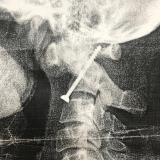

Изображение

Имплант восстанавливает слух Самый успешный нейроимплант нашего века – искусственная улитка, вызывающая звуковые ощущения. Для больных с тяжелой потерей слуха, у которых поврежден слуховой нерв, существует имплант, электрически стимулирующий ствол головного мозга. Это жесткое устройство не всегда обеспечивают надежный электрический контакт с тканью ствола, что приводит к побочным эффектам,... продолжение →